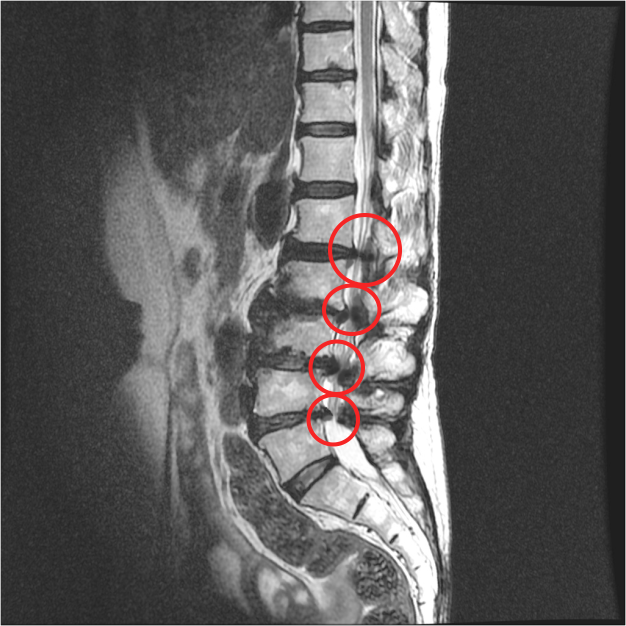

협착증 치료에 대한 잘못된 생각 두 번째, 치료만 하면 끝이라는 생각입니다. 많은 분들이 협착증 치료는 원인을 깨끗하게 해결할 거라고 기대합니다. 그래서 치료만 받으면 다 끝난다고 생각하니까 치료에 대해 조급증을 갖습니다. 그래서 조급하게 치료를 결정하고, 치료를 받고 나면 모든 게 끝날 거라 기대합니다. 이 경우 무엇이 문제가 되느냐? 모든 게 끝났다고 생각하니까 관리를 안 하고, 이게 많은 문제를 일으킬 수 있습니다. 한번 늙어버린 건 다시 젊어지지 않으므로, 치료 후에 어떤 치료를 받고 좋아졌든 지속적인 세심한 관리와 재활운동이 반드시 필요합니다. 치료만 받으면 끝이라고 생각하고 조급함을 가질 경우 생길 수 있는 문제를 먼저 수술 후 발생할 수 있는 문제부터 말씀 드리겠습니다. 협착증 수술은 문제를 일으키는 가장 큰 원인인 퇴행된 척추관 내의 황색인대를 제거하게 되는데, 퇴행이 가장 심한 부분을 수술로 제거하고 나사를 박아 고정시키게 됩니다.

그런데, 보시면 협착증은 이 부분만이 아니라 주변 부분도 다 퇴행되어 있습니다. 그래서 고정술을 한 이후에 이 부분이 구부리지도 펴지도 못하게 되기 때문에 이미 퇴행된 주변 마디에 부담을 주게 됩니다. 주변 마디가 더 많이 구부렸다 폈다가 해줘야 하는 것이죠. 그런데 앞서 말했듯이 협착증 환자는 이미 주변 위아래 마디도 퇴행되어 약해진 상태인데, 추가적으로 부담을 주니까 시간이 흐르면 주변 부위도 문제가 생기게 되는데요. 이것을 인접분절질환이라고 합니다. 일반적으로 척추유합술 후 이러한 문제가 많이 발생하기 때문에 인접분절질환이라는 이름까지 만들어져 있습니다. 이러한 인접분절질환은 특히 수술 후 관리를 잘 못하면 당연히 더 잘 생기기 때문에 유합술을 했다면, 이 인접분절질환이 생기지 않도록 관리를 세심하게 잘 해줘야 합니다.

모커리 협착증 치료 이후에는 환자분들의 걷는 거리도 늘어나고, 걷는 것도 편해지고, 굽어진 허리도 많이 펴집니다. 그런데 그렇다고 해도 늙고 변성된 허리가 젊어진 것은 아닙니다. 어떤 환자분들은 치료 받고 좋아지니까 'MRI를 찍어보면 척추관이 넓어지지 않았을까?' 생각하시고 MRI 한 번 찍어보자 이러시는 분들도 꽤 있는데, 아닙니다. 늙은 허리가 젊어진 게 아니고, 척추관의 구멍이 넓어진 것도 아닙니다. 통증치료와 재활치료를 통해 허리의 약해진 기능을 보강한 것입니다. 그래서 치료를 받은 후에도 무리하면 상태가 다시 나빠질 가능성이 있기 때문에 지속적인 세심한 관리와 꾸준한 재활운동이 필요합니다. 이 때문에 저희는 환자분들에게 치료 후 운동과 생활관리에 대한 중요성을 입원치료기간 중에 꼼꼼하게 교육합니다. 실제로 치료 이후에도 지속적으로 세심하게 관리하고 꾸준히 운동하신 분들은 치료 이후 호전 효과를 오랫동안, 장기간 유지할 수 있습니다. 그러니 여러분, 치료만 받으면 끝난다는 생각으로 조급증을 갖지 마시고, 협착증은 지속적인 관리가 필요한 질환이라는 걸 꼭 아시길 바랍니다.